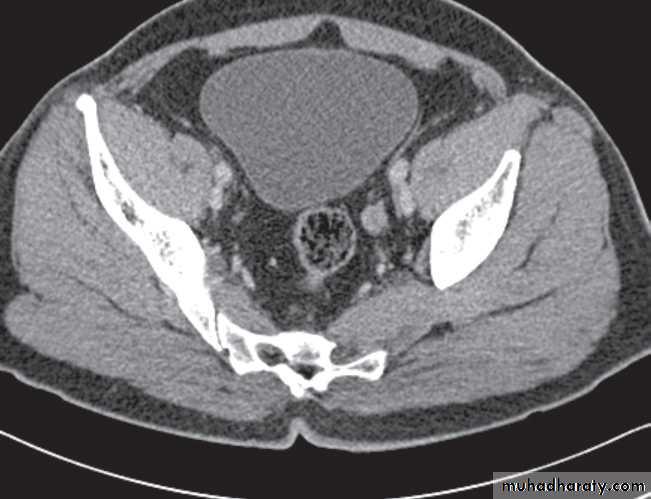

Computed tomography without intravenous contrast medium is exquisitely sensitive for the detection of calculi.

It is used in place of IVU for the detection and precise anatomical localization of stones prior to treatment in most centres

Computed tomography is now widely used to evaluate urinary tract obstruction .In acute obstruction, non-contrast enhanced CT sensitively demonstrates calculi and the unopacified, dilated collecting system can frequently be traced down to the point of obstruction .

Non-contrast CT is often used in acute ureteric colic, as an alternative to IVU, in patients with an allergy to intravenous contrast medium.